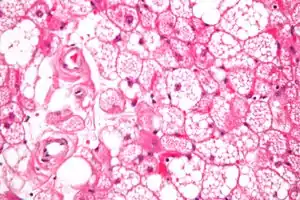

![]() Мікрофотознімок гіберноми (фарбування г-е). Мікрофотознімок гіберноми (фарбування г-е). | |

Гібернома визначається у вигляді вузлового утворення. Вузол складають часточки, що утворюють круглі або полігональні клітини. Ці клітини мають жирові вакуолі, завдяки яким ці клітини характеризуються зернистою або пінистою цитоплазмою.

- Часточковий тип. Характеризується різними рівнем диференціації клітин, що можуть бути круглими, овальними з гранулярними еозинофільними клітинами та добреокресленими мембранами, що перемішані з мультивакуольними жировими клітинами. При цьому типі клітин визначається центрально розташоване ядро без ознак плеоморфізму